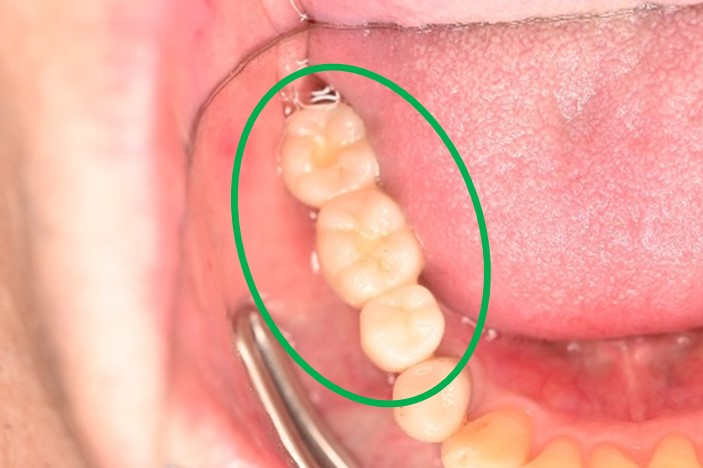

男性 Kさん 60代 (インプラント)

主訴

右下に1本の義歯を入れていたが、インプラントにしたい。

治療内容

インプラントを埋入しました。

所感

2026年2月9日にインプラント埋入手術をし、5月1日に最終的な被せ物を入れました。ブリッジや義歯は、歯がないところに掛かる力を、他の歯が支えることになります。インプラントは、他の歯に負担をかけることはありません。一本欠損になってしまったときは、1本だけインプラントを入れて、他の歯を護り、それ以上歯を失わないことが大切になります。

インプラント:¥363,000(税込)

Before

After